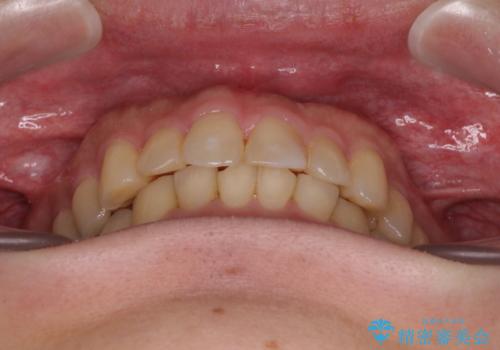

- 深い咬み合わせによる食いしばりで、顎関節や頭が痛むことがあるとのことで来院された患者様です。

歯ぎしりができないくらい強い食いしばりの咬合状態であったため、奥歯の歯軸を起き上がらせることで咬合を挙上させ、歯ぎしりができるようにしていくこととしました。

下顎が左側にずれているため、上下正中は最大限合わせられるところまで合わせるゴールとなりました。